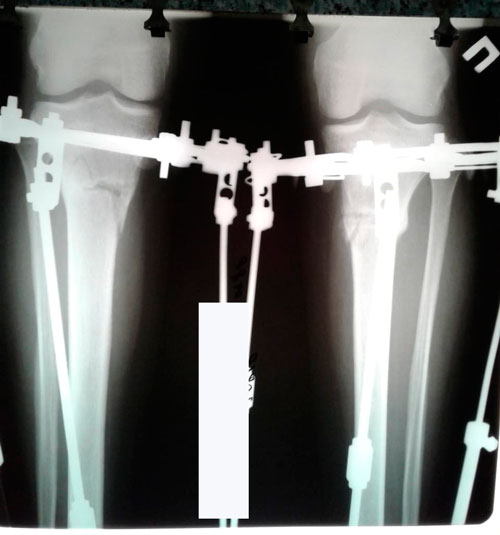

Рентген в 78 дней.

Вложения

IMG-20180803-WA0007.jpg

IMG-20180803-WA0006.jpg